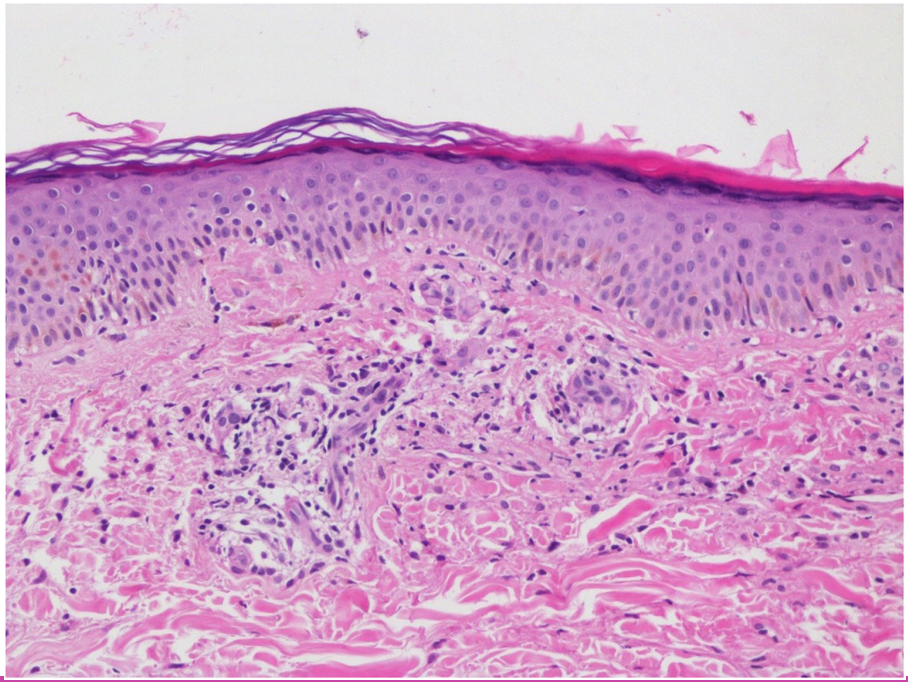

A 60-year-old female with seropositive rheumatoid arthritis on methotrexate, leflunomide, sulfasalazine, and prednisolone presented to the clinic with worsening symptoms despite combined conventional synthetic diseasemodifying antirheumatic drug (DMARD) therapy. Her history included total thyroidectomy and hypertension. Examination revealed 4 tender and 2 swollen joints, with no other abnormalities. Laboratory tests showed C-reactive protein was 19.64 mg/L, and erythrocyte sedimentation rate was 31 mm/hour. Due to high disease activity (Disease Activity Score 28: 5.97), etanercept was started. In the second month of etanercept treatment, the patient developed rashes on both lower extremities (Figure 1A). Physical examination and all laboratory tests, including complete blood count, biochemical tests, autoantibody profiles, complement levels, and viral serologies (hepatitis and HIV), were normal. A dermatology consultation was obtained, and a skin biopsy was performed, revealing findings consistent with PPD (Figure 2). Topical corticosteroids provided partial relief but did not fully resolve the rashes. Given the temporal relationship between etanercept and the development of rashes, the drug was stopped, and adalimumab was started. Therapy was discontinued due to continued joint pain and the persistence of rashes while on adalimumab, and an interleukin-6 inhibitor, tocilizumab, was initiated. At the 1-month follow-up after starting tocilizumab, a notable improvement in rashes was documented (Figure 1). Long-term follow-up is ongoing. Informed consent for publication was obtained from the patient.

The etiology of PPD is not fully understood, but its pathogenesis is thought to be driven by cell-mediated immune mechanisms.[1] Drugs such as statins, beta-blockers, calcium channel blockers, aspirin, and diuretics have been associated with PPD.[3,4] The strength of the association between the drug and the adverse reaction was evaluated using the Naranjo Adverse Drug Reaction Probability Scale. Scores ≥5 to 8 on this scale indicate a “probable” relationship, while scores ≥9 indicate a “definite” relationship. A Naranjo score of 6 confirmed a probable association between the rash and TNF-α inhibitors.[5] It is a rare disease, having been reported in just 2 cases associated with the use of TNF-α inhibitors.[6,7] In one of these 2 cases, the trigger was promoted by non-TNF, while in the other case, the trigger was TNF, and with the discontinuation of the drug, the lesions were resolved.[8] The persistence of rashes in this case parallels findings from previously reported cases, emphasizing the potential class effect of TNF-α inhibitors. PPD should be distinguished from vasculitis and similar conditions, and a skin biopsy serves as a valuable diagnostic tool.[4] In this case, at the 1-month follow-up visit at which the tocilizumab therapy was initiated, rashes almost completely regressed (Figure 1B), and the follow-up process is still ongoing. This case highlights the importance of careful monitoring for skin reactions in patients receiving TNF-α inhibitors and emphasizes the need for a multidisciplinary approach to ensure optimal management.